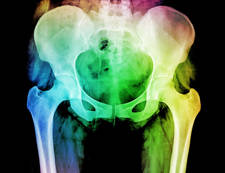

Leer másDISFUNCIÓN SACROILÍACA. Una causa frecuente de dolor lumbar.

Leer másSíndrome del músculo piramidal